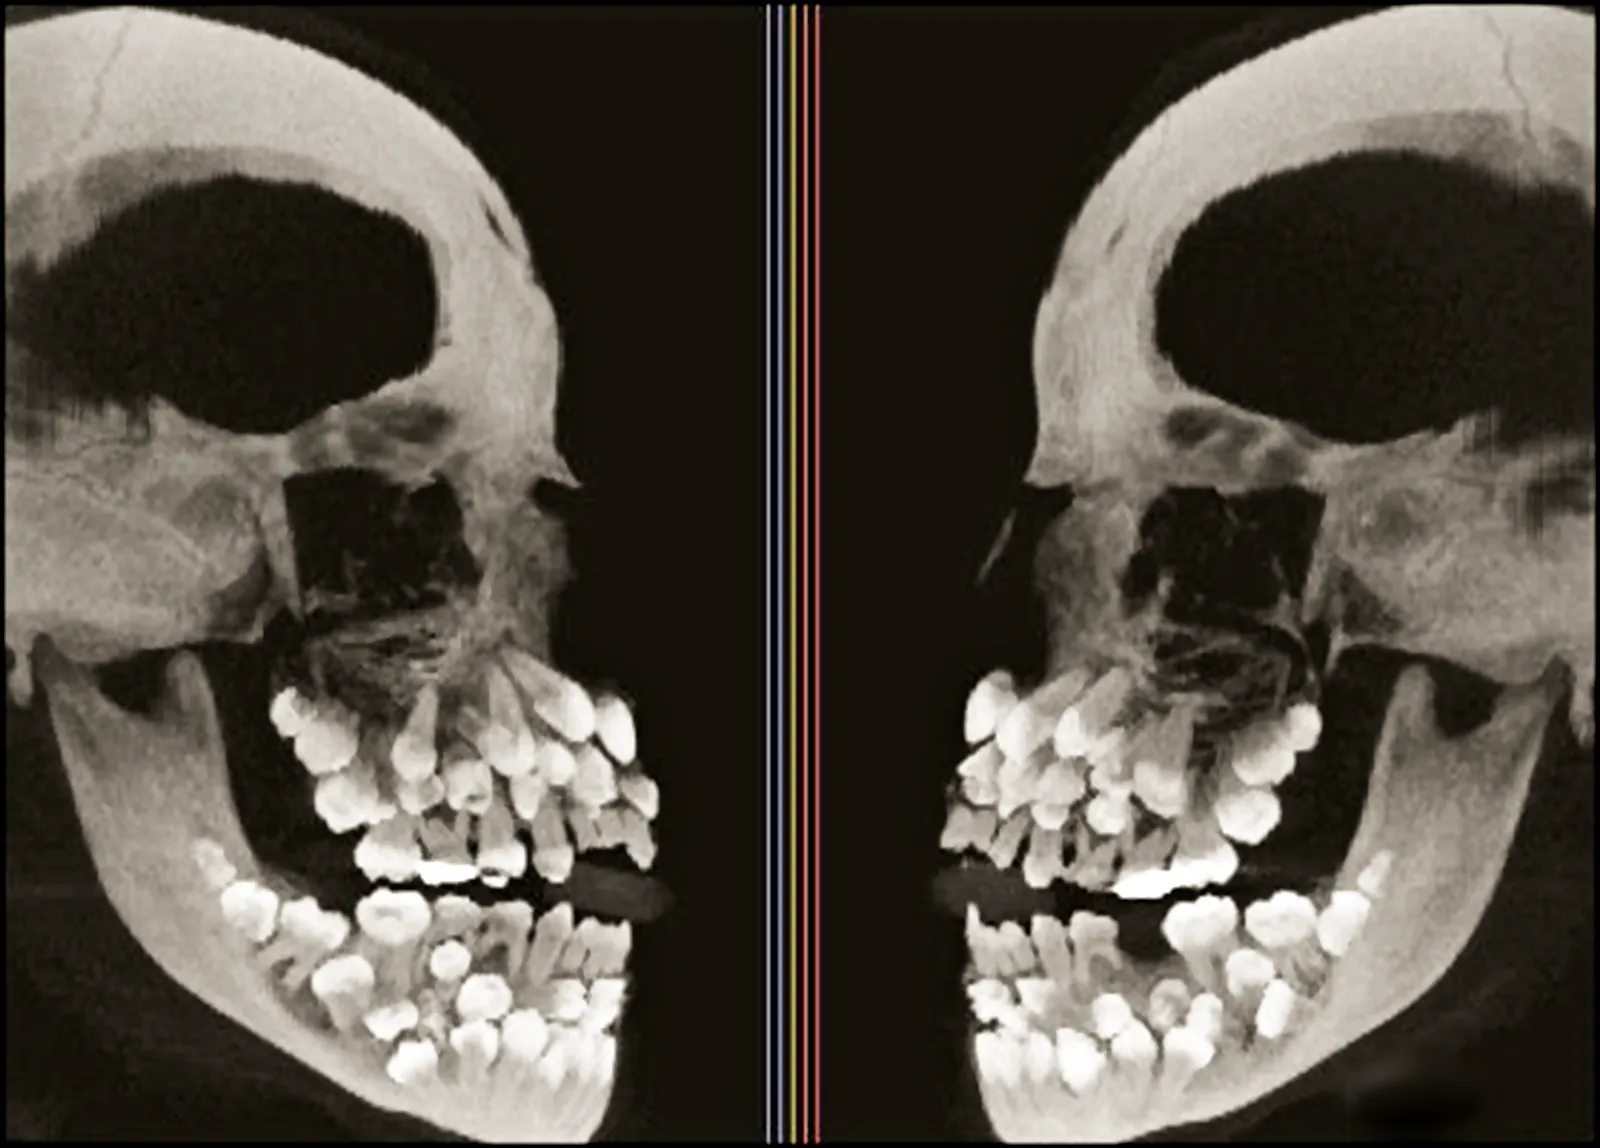

Рентгеновский снимок человека с гипердонтией

Фото imgur